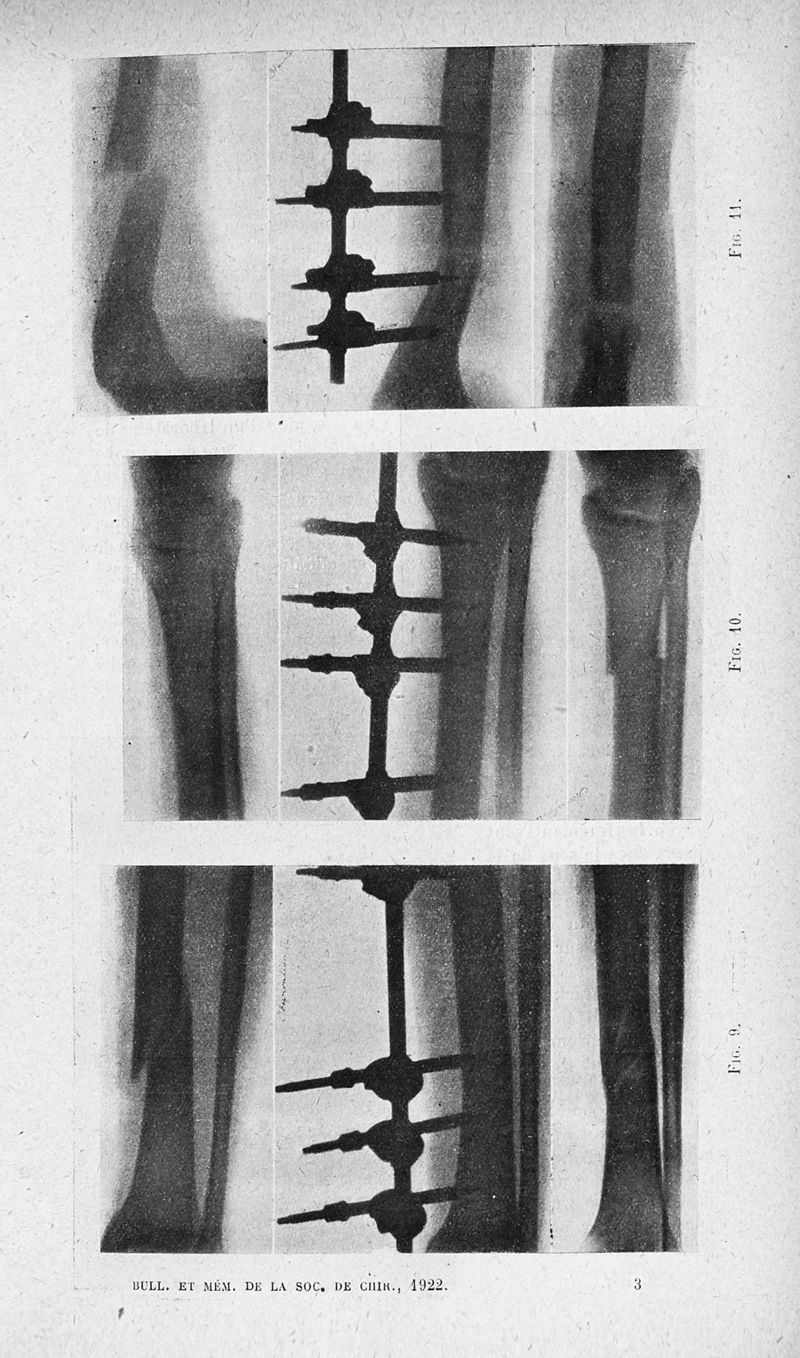

Bulletins et mémoires de la société de chirurgie de Paris

Tome XLVIII, 1922. - Paris : Masson, 1922.